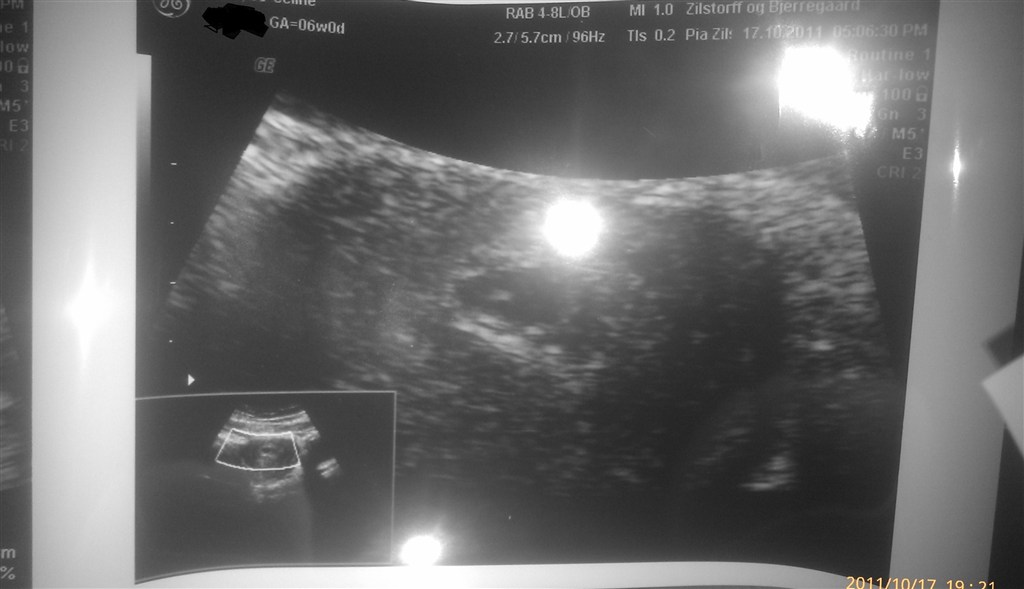

Er så blevet scannet idag og det SÅ godt ud <3 Er dog mindre henne end beregnet. Hun beregnede mig til 5+4, og hun var så sød at give os en til scanning for samme pris om 2 uger.

Hun så hjerteblink og vi så det også <3 SÅ FANTASTISK <3

Her kommer lige et billede af den lille bebse (som ligner en lille svømmende fisk på vores DVD) .. også dejligt og en overraskelse at jeg skulle scannes udefra